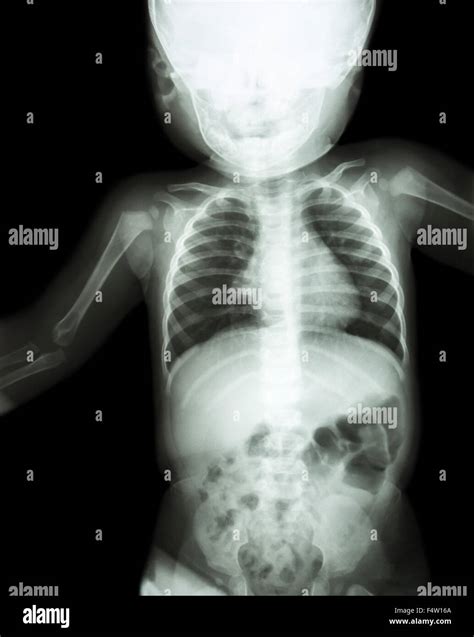

Infant X-ray imaging is a critical diagnostic tool in pediatric medicine, providing valuable insights into the health and development of young patients. This non-invasive procedure allows healthcare professionals to visualize internal structures, detect abnormalities, and guide treatment plans. Understanding the importance, process, and safety measures associated with infant X-ray imaging is essential for both medical professionals and parents.

Infant X-ray imaging involves the use of low-dose radiation to produce images of the internal body structures. This technique is particularly useful for diagnosing conditions such as fractures, pneumonia, and congenital anomalies. The process is quick and relatively painless, making it suitable for infants who may be too young to cooperate with more complex diagnostic procedures.

• Diagnosis of Respiratory Conditions: Conditions like pneumonia can be detected through chest X-rays, allowing for timely intervention.

• Assessment of Congenital Anomalies: X-rays can help identify congenital anomalies, such as heart defects or skeletal abnormalities, which may require immediate medical attention.

Pneumonia Chest X-rays can detect pneumonia, an infection of the lungs, by showing areas of inflammation or fluid buildup.

Congenital Anomalies X-rays can reveal congenital anomalies, such as heart defects or skeletal abnormalities, which may require immediate medical attention.

Foreign Bodies X-rays can locate foreign bodies, such as swallowed objects or inhaled items, which may require removal.